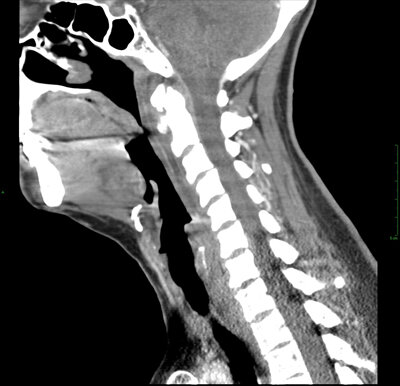

КТ шейного отдела позвоночника – это многофункциональное исследование, которое позволяет за одно сканирование оценить состояние позвонков и межпозвоночных дисков, связок, мышц, нервных окончаний, лимфоузлов, кровеносных сосудов и мягких тканей в области шеи. По количеству и качеству информации, мультиспиральная компьютерная томография или МСКТ значительно превосходит обычную рентгенографию.

В обычном рентген-аппарате источник излучения статичен, из-за чего удается получить только двухмерные снимки. Изображения органов, находящихся на одной линии накладываются друг на друга, затрудняя постановку диагноза. Компьютерная томография шейного отдела позвоночника позволяет получать серии детальных, послойных снимков с шагом сканирования в 1-2 мм. Это становится возможным благодаря подвижным источникам рентген-лучей, просвечивающим тело пациента под разными углами, чувствительным датчикам, и последующей компьютерной обработке. Компьютер не только формирует снимки, но и выстраивает трехмерную модель шейного отдела позвоночника, облегчая врачу работу по выявлению костных патологий.